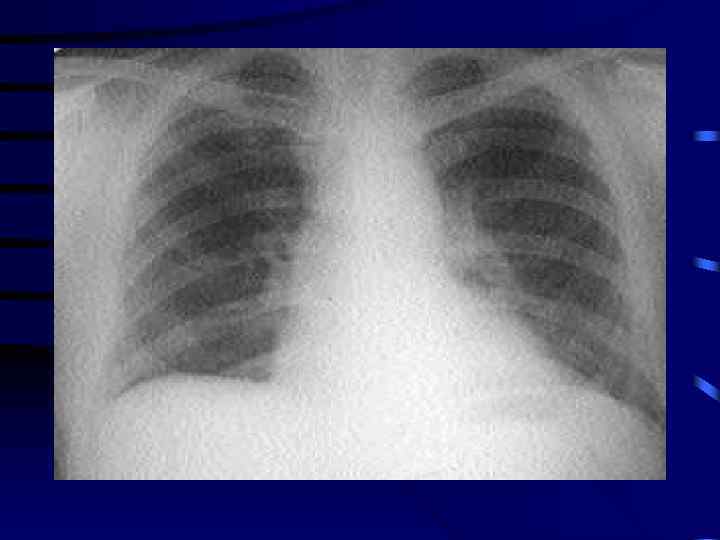

Медицина и диагностика: Аномалии ребер на рентгене